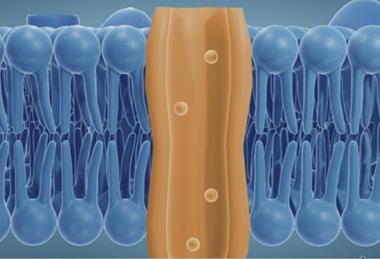

Physics-based modelling offers a new way to study drug targets

Australian start-up OmnigeniQ has demonstrated what it describes as the first deterministic, physics-based computation of a human protein in its native state.